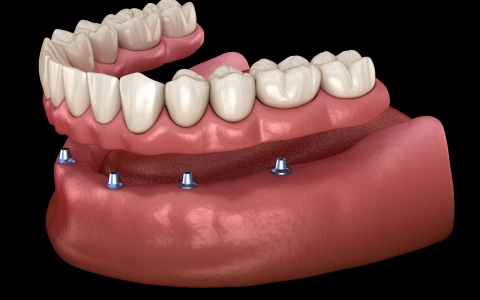

All-on-four İmplant Tedavisi

All-on-4/6, tam dişsiz çenede 4–6 implantla aynı gün sabit, estetik ve fonksiyonel diş sağlayan, kemik grefti ihtiyacını azaltan tedavidir.